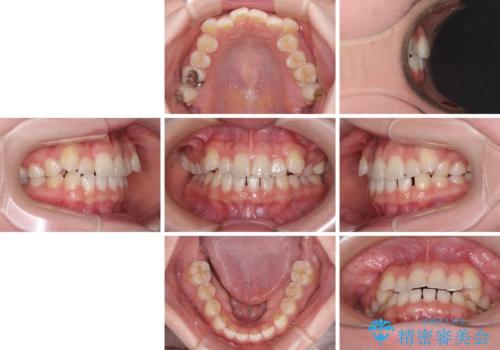

- 八重歯を気にして来院された患者様です。

口腔内の状況を確認したところ、左右ともに下顎第二大臼歯が欠損しており、咬み合うべき上顎の第二大臼歯が著しく挺出していました。

挺出した大臼歯を元の位置に戻すことは現実的に難しいため抜歯することとし、補助装置とワイヤー装置により上顎歯列全体を後方に移動することとしました。

順調に後方移動することができ、わずか1年強で治療を終えることができました。